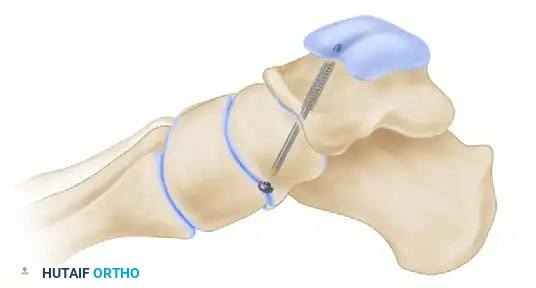

التثبيت باستخدام المسامير المعدنية

بمجرد الوصول إلى الوضع المثالي، يبدأ الجراح بتثبيت المفاصل. يتم تثبيت المفصل الكاحلي الزورقي أولا باستخدام مسامير إسفنجية كبيرة مجوفة يتم إدخالها عبر أسلاك توجيهية تحت إرشاد الأشعة السينية المباشرة لضمان الدقة المتناهية.

بعد ذلك، يتم تثبيت المفصل العقبي النردي ومفصل تحت الكاحل بمسامير مماثلة، مع التأكد من انضغاط أسطح العظام بقوة ضد بعضها البعض لتعزيز عملية الالتحام.